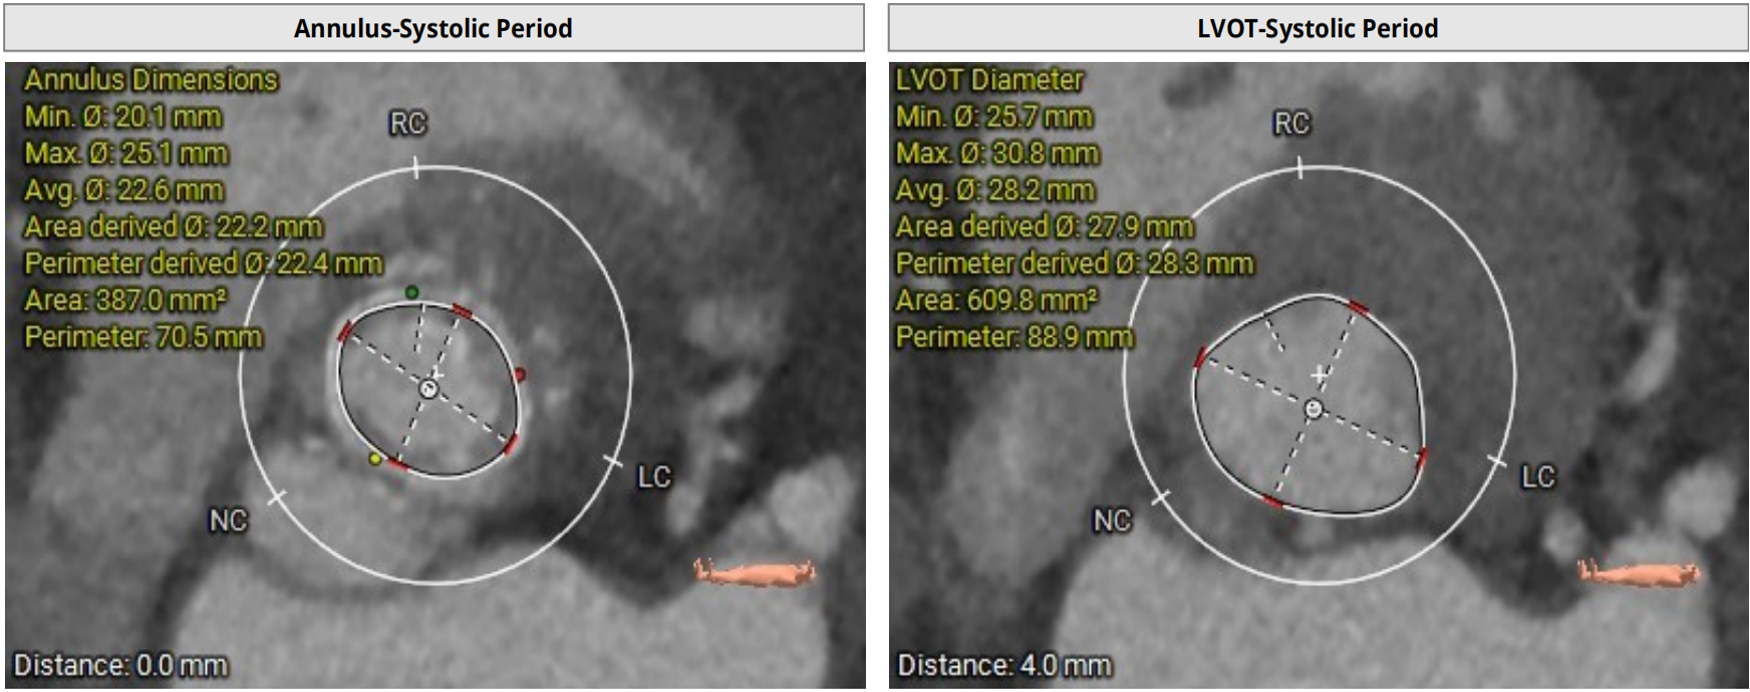

2D echo suggestive of severe aortic regurgitation. CT analysis done and we decided to opt for 24mm TAVR valve